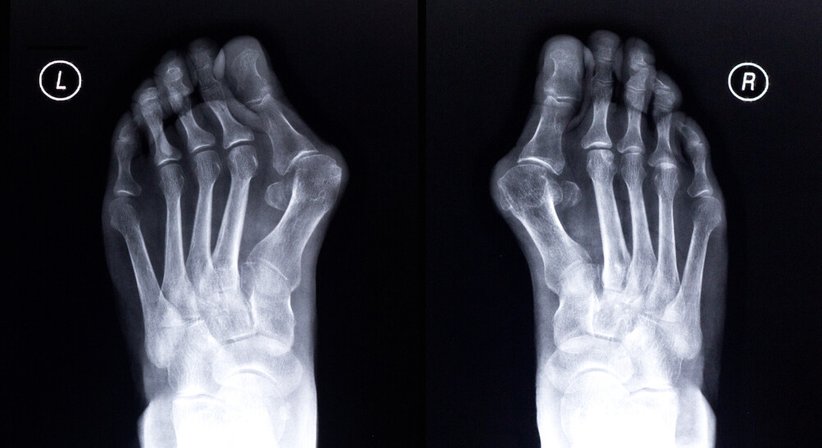

Der Hallux valgus ist die häufigste Fehlstellung des Fußes. Es handelt sich um eine Fehlstellung des Großzehengrundgelenks, bei welcher die Großzehe von ihrer normalen Ausrichtung nach außen abweicht und andere Zehen verdrängt. Typisch für einen Hallux valgus ist, dass das oft geschwollene Mittelfußköpfchen im Bereich vom Großzehengrundgelenk hervortritt und schmerzhaft gegen den Schuh drückt.